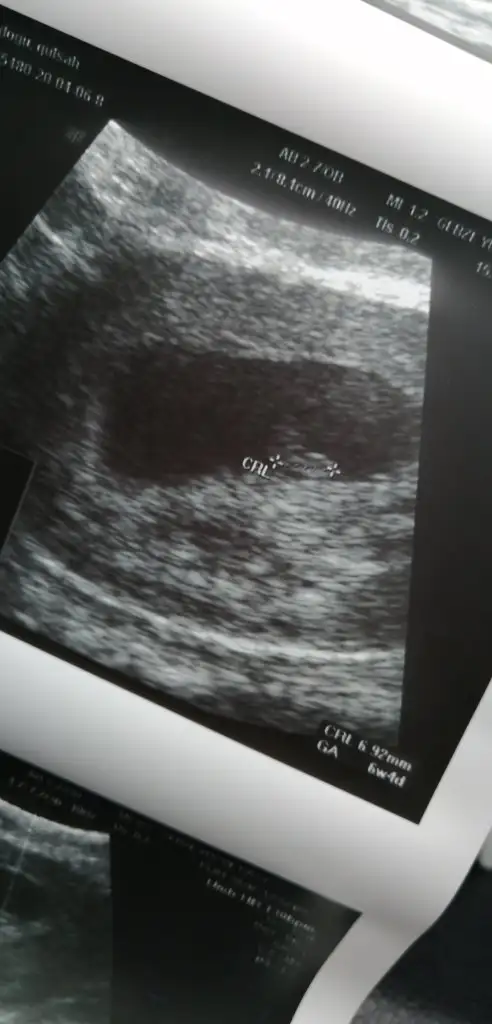

Inşallah canım inan çok üzüldüm.bende kendi capimda netten araştırdım.insallah güzel olur her seyKizlar az once bi doktor akrabamiz var yurtdisinda onunla konustum Boyle yuksek degerlerde o kadar hizli yukselmezmis 2gun icin normal dedi 8haftani bekle ultrasona git dedi kendi doktorumda normal dedi